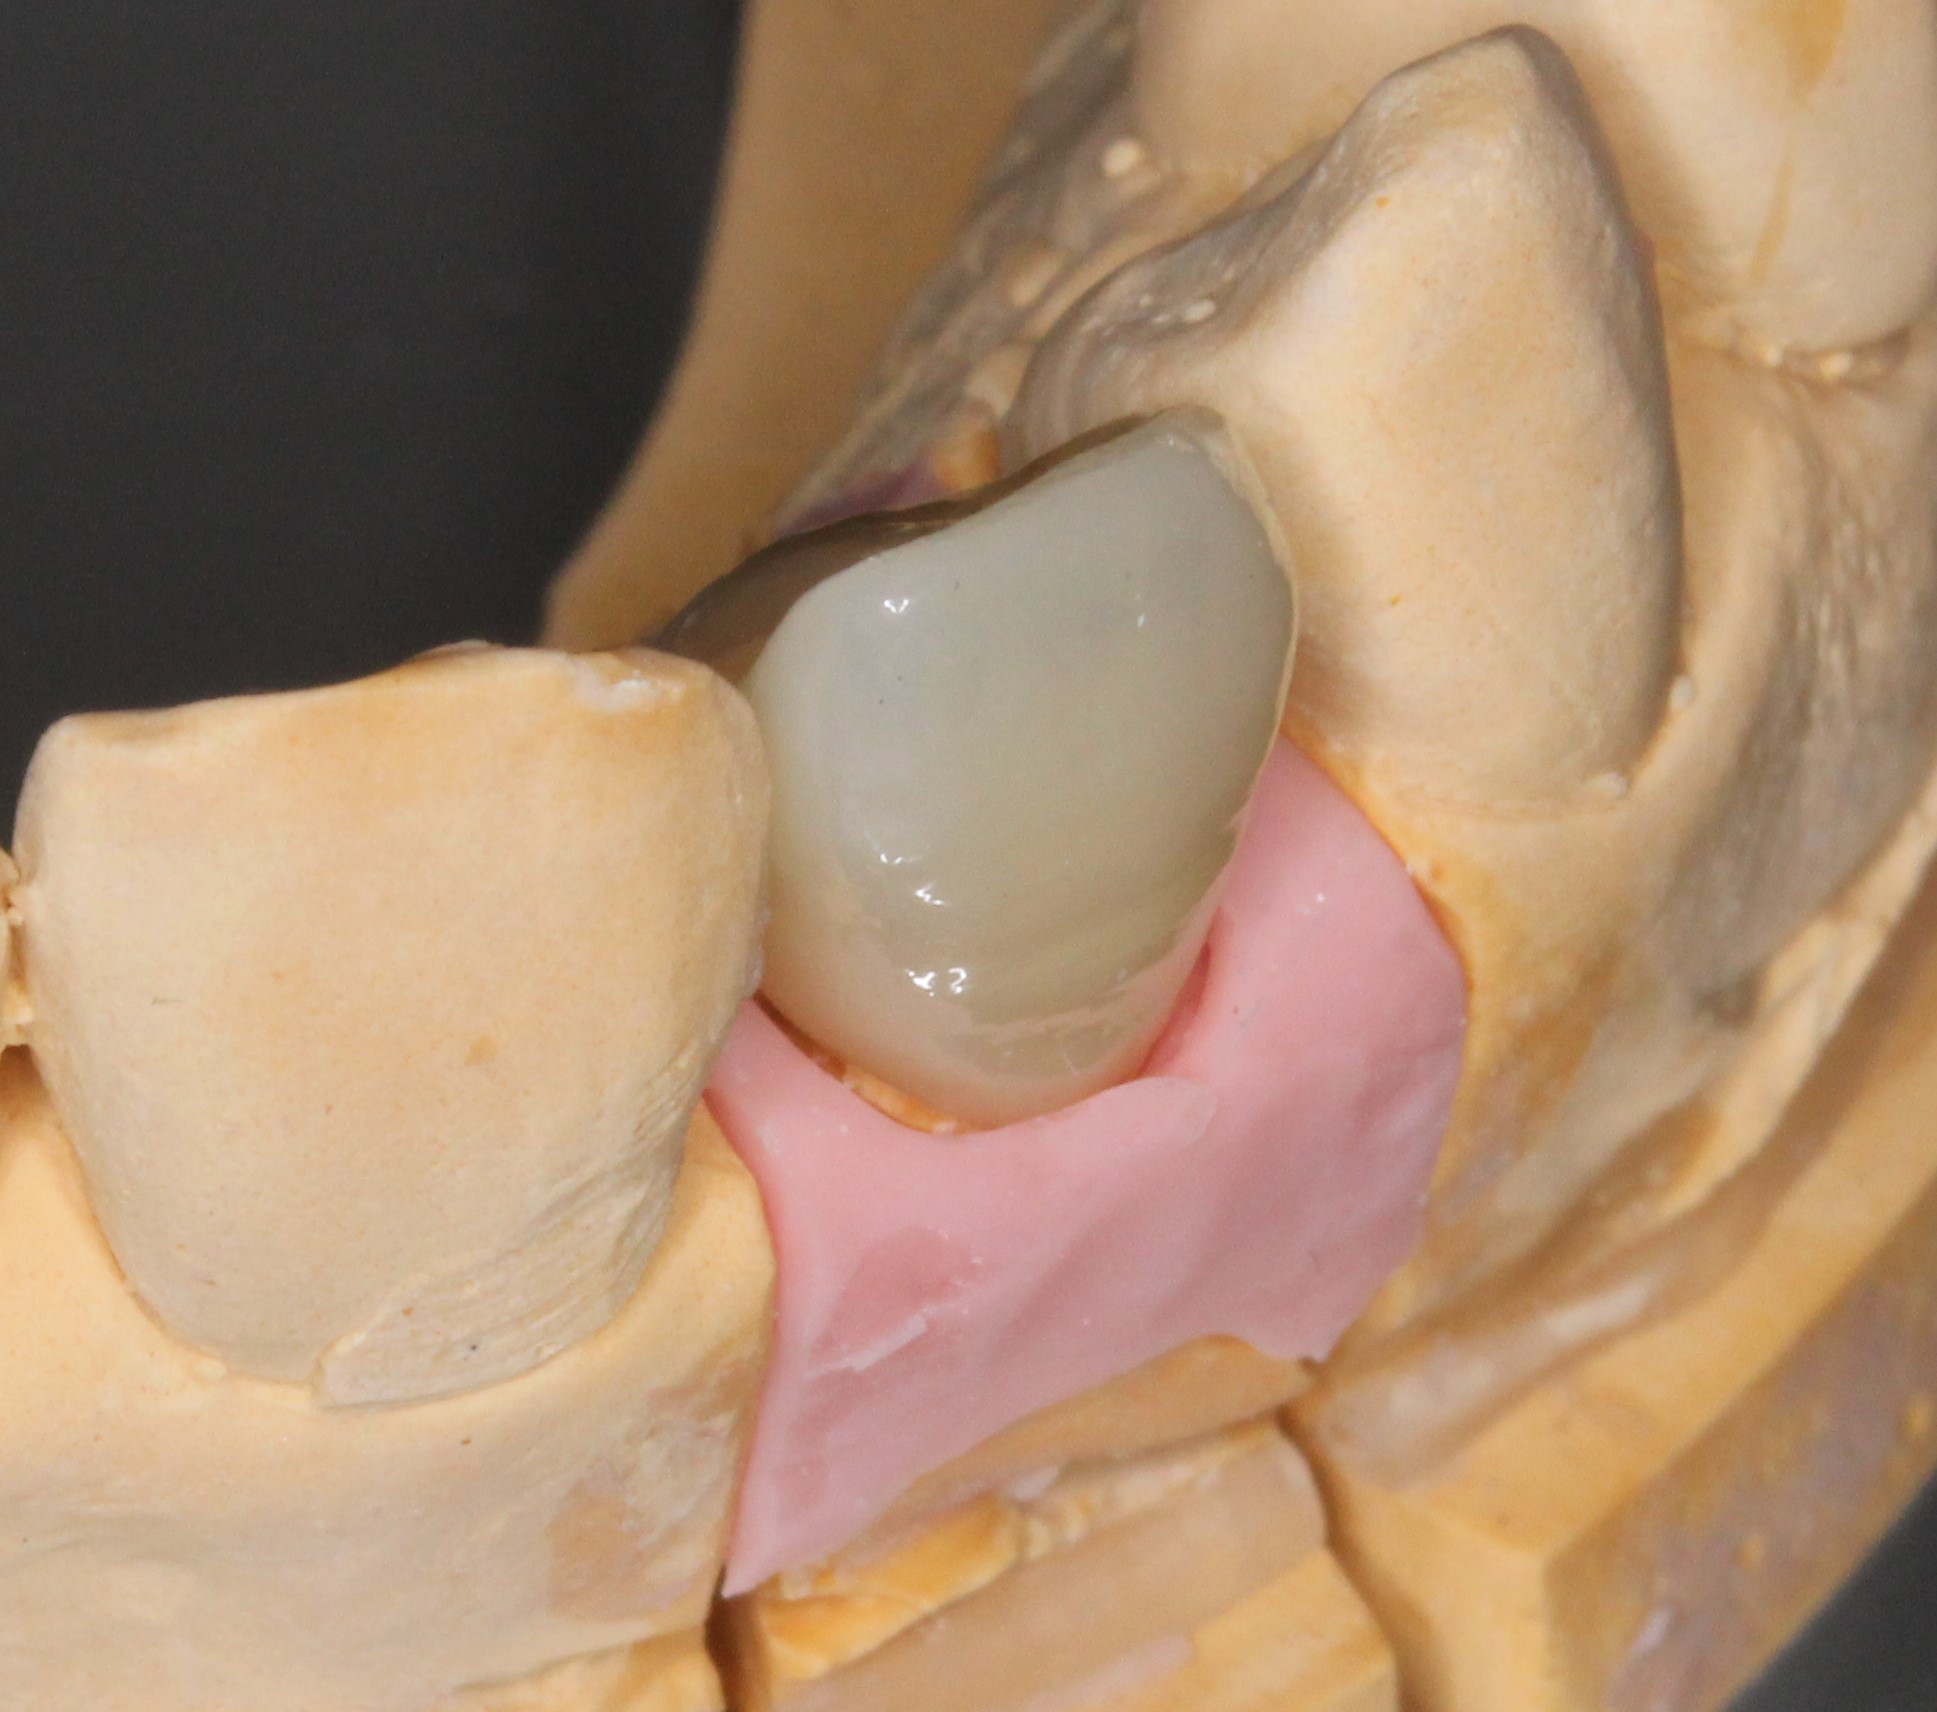

周囲歯牙形態、色調にバッチリと合わせられないと、被せ物の部分だけ目立ち造り物感がでてしまいます。

また、周囲歯肉の操作も同時に行う必要があります。

歯と歯のつけねの間の隙間(ブラックトライアングル)ができないような歯肉の取り扱いや、

被せ物と歯牙の移行部(マージン)が、歯肉内に1~1.5mm程の所にくるように設定いたします。

口腔内写真を撮影し、周囲歯牙との形態的なバランス、色調を完璧に合わせます。

これらの条件がすべて整うと、とても綺麗な見た目が再現できます。